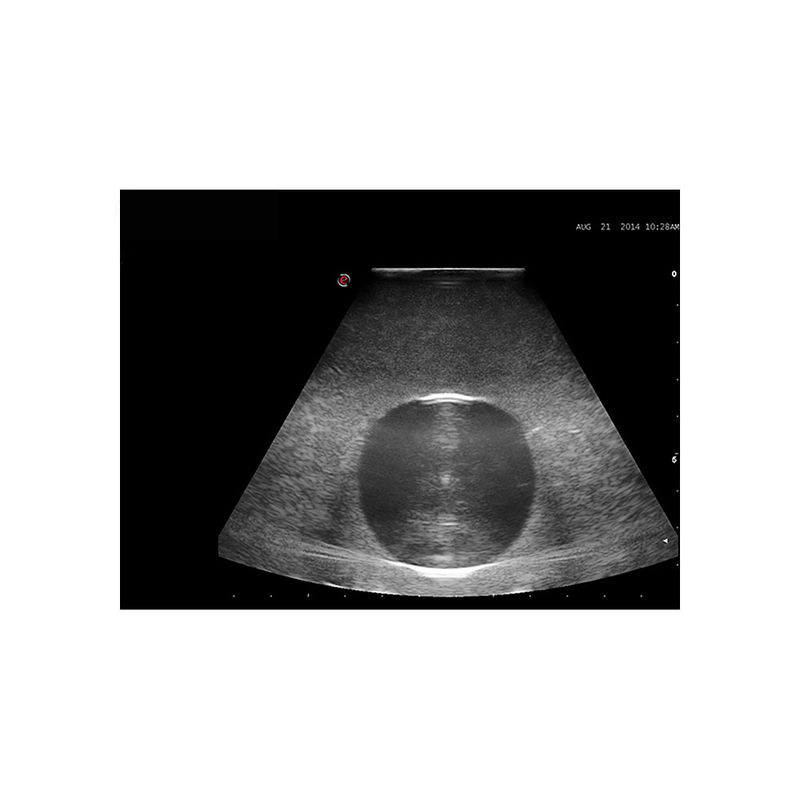

超声引导下囊肿穿刺引流模型

型号:PC-BP030

模型为培训超声引导下囊肿穿刺引流而专门设计的模型,适用于外科以及超声影像科的教学与培训。